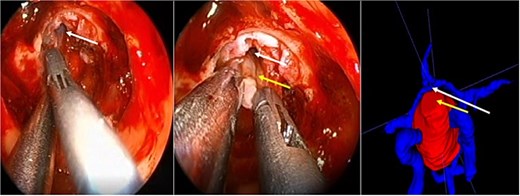

A 71-year-old woman who gradually began with bitemporal hemianopia, progressing to amaurosis of the right eye, adding diabetes insipidus. An MRI study obtained the following images (Fig. 1). 3D reconstruction was performed by manual segmentation to obtain the anatomy of the tumor and its vascular relationships. For this segmentation, it was necessary to splice T2, T1, Contrast, and 3D TOF sequences (Fig. 2). The importance of the reconstruction lies in being able to adequately observe most of the cerebral blood circle and its relationships with the tumor. At the time of carrying out the transnasal resection surgery and keeping in mind the proximity of the anterior communicating artery with the dorso-ventral region of the tumor, the capsule was resected with excessive caution to avoid generating excessive traction and thus avoiding injuries—important vascular (Fig. 3).

3D reconstruction through manual planimetric segmentation of the tumor and its vascular relationships. White arrow, left internal carotid artery. Yellow arrow, anterior cerebral artery segment A2. Red arrow, anterior communicating artery.